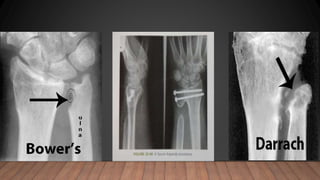

ULNAR SIDED PROCEDURES

• Indications : persistent pain ,rotational contracture ,instability of DRUJ ,

BOWER ‘S PROCEDURE :

- Hemiresection interposition arthroplasty of DRUJ

- ie excision of substantial portion of ulnar head leaving ulnar styloid , TFCC ,

ulnar column of cortex

SAUVE – KAPANDJI PROCEDURE :

- A segment of the ulna is excised at the level of ulnar neck

DARRACH ‘ S PROCEDURE :

-excision of distal end of ulna ,at the proximal end of sigmoid notch

Ulnarshortening :

• Indicated in symmptomatic ulnocarpel impingement after distal radius fract

Ulnar head replacement

• salvage procedure ,in painful radioulnar impingement following failed darrach

or sauve kapandnji procedure